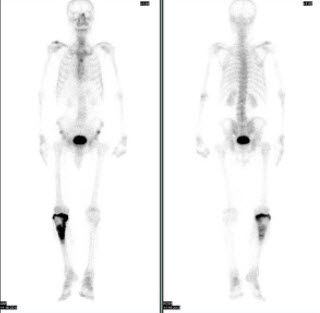

99、多项选择题

患者48岁,右乳癌术后7年,感颈部疼痛2个月,行99Tcm-MDP骨显像如图,可能的诊断是()

A.大致正常的影像

B.下位颈椎有病理性骨折

C.下位颈椎有骨转移

D.双侧股骨远端骨转移瘤

E.骨质疏松征象

278、多项选择题

男,69岁,肺癌化疗中,诉下肢疼痛3个月,行全身骨显像如图,可能的诊断()

A.未见骨转移征象

B.双侧膝关节转移瘤

C.双侧胫骨转移瘤

D.双下肢肥大性骨关节病

E.有“热髌征”